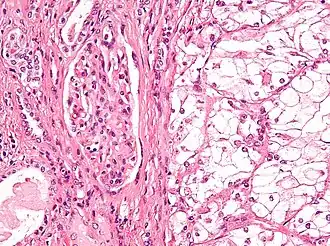

Микрофотография, демонстрирующая наиболее частый тип рака почки — светлоклеточный (окраска гематоксилином и эозином) | |

Ранее рак почки классифицировали по типу клеток и характеру роста. Позже было установлено что рак почки в абсолютном большинстве — смешанный. Современная классификация основывается на морфологических, цитогенетических и молекулярных исследованиях, а также иммуногистохимическом анализе и выделяет 5 видов почечно-клеточного рака[35]:

- светлоклеточный рак почки

- папиллярный (1 и 2 подтип) рак почки

- хромофобный рак почки

- онкоцитома почки

- рак собирательных трубочек

- медуллярный рак почки

Папиллярный почечно-клеточный рак при этом включает два отдельных подтипа: 1-й из них представлен мелкими клетками со светлой цитоплазмой, 2-й — крупными клетками и эозинофильной цитоплазмой (для данного подтипа вероятность развития метастазов выше)[17].

В рамках упоминавшегося выше многоцентрового кооперированного исследования 2012 года гистологический тип опухоли почки после операции был описан у 7357 из 7813 больных раком почки, присутствовавших в базе данных. При этом светлоклеточный вариант рака был выявлен у 6774 (92,1 %) пациентов, папиллярный — у 303 (4,1 %), хромофобный — у 175 (2,4 %), рак собирательных трубочек — у 17 (0,2 %), а наличие саркомоподобного рака в опухоли отмечалось у 88 пациентов. Частота выявления светлоклеточных и несветлоклеточных форм почечно-клеточного рака заметно отличалась от данных, полученных в начале 2000-х гг. в зарубежной клинической практике (где на долю светлоклеточного варианта приходилось 80—90 % злокачественных опухолей, папиллярного — 10—15 %, хромофобного — 4—5 %, рака из собирательных трубочек — менее 1 %, а 7 % случаев осталось неклассифицированными[17]); это, возможно, связано с определённой недооценкой частоты хромофобного и особенно папиллярного вариантов, допускаемой российскими морфологами[34].